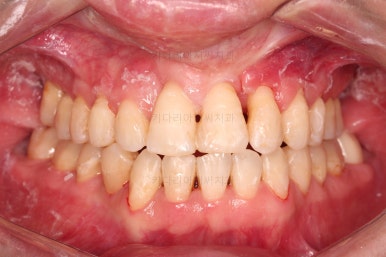

부산구순구개열교정 종료 시의 입안의 모습입니다.

위아랫니 정렬이 잘 되었고, 치아 갯수가 위아래가 다르지만 교합도 나쁘지 않게 마무리가 되었습니다.

대문니 2개가 예후가 안좋긴 하나 양옆 치아들과 유지철사로 부착해 두어 최대한 오래 조심히 써보기로 했습니다.

치열이 정렬이 잘 되었고요.

웃을 때 보이는 치열의 느낌, 얼굴과의 조화 등 모든 부분이 좋아졌습니다.